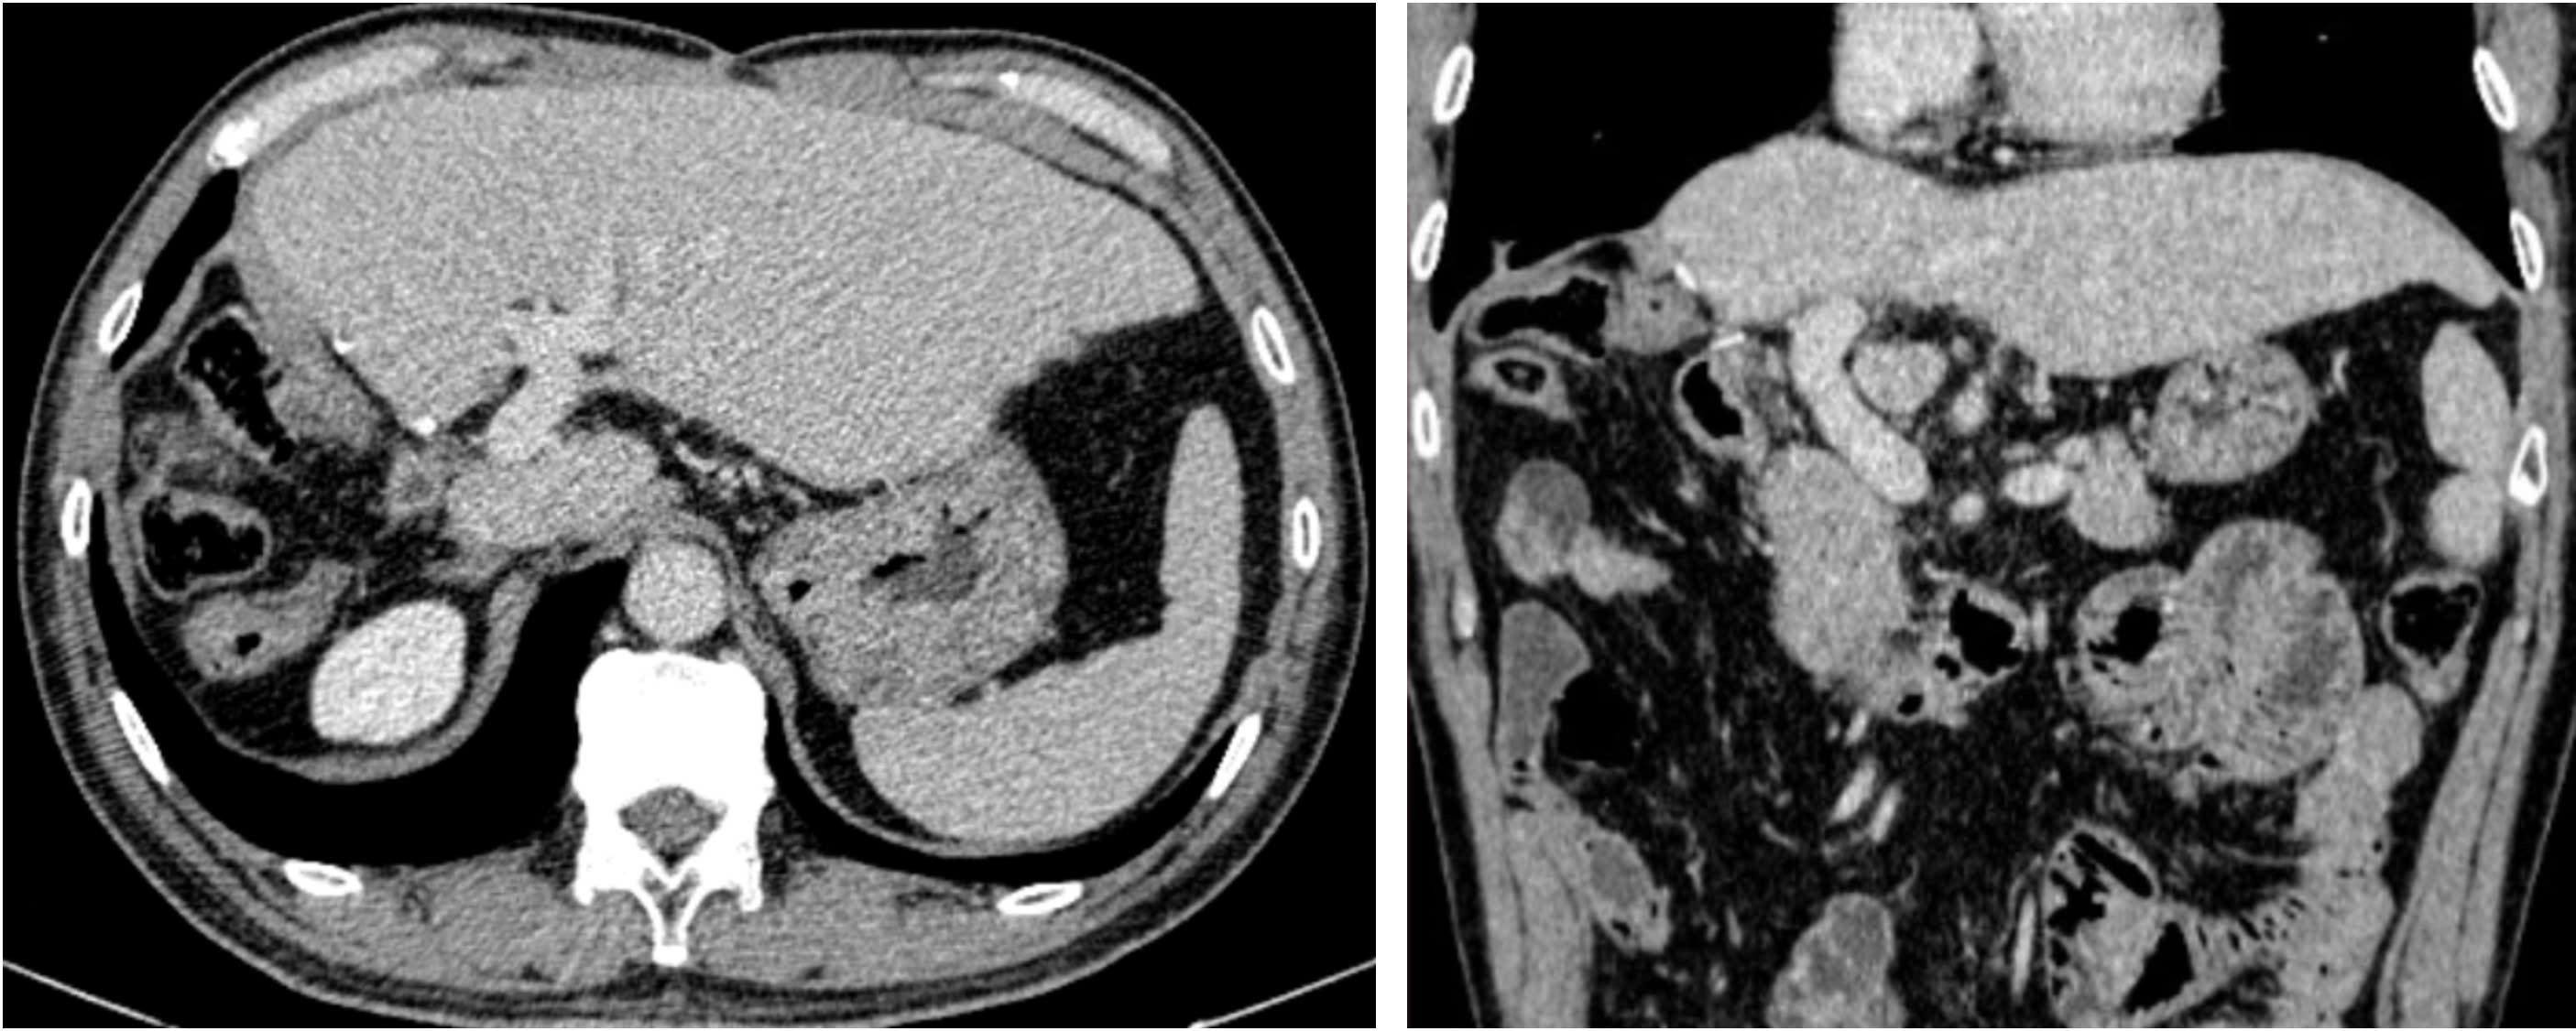

Hình ảnh chụp cắt lớp vi tính sau phẫu thuật 4 năm. Bệnh nhân gan trái tốt, tĩnh mạch cửa thông thoáng, không có tái phát tại gan và di căn xa.